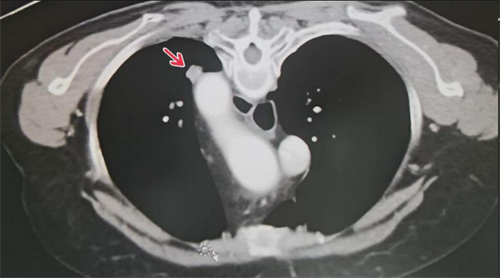

肺转移瘤邻近大血管